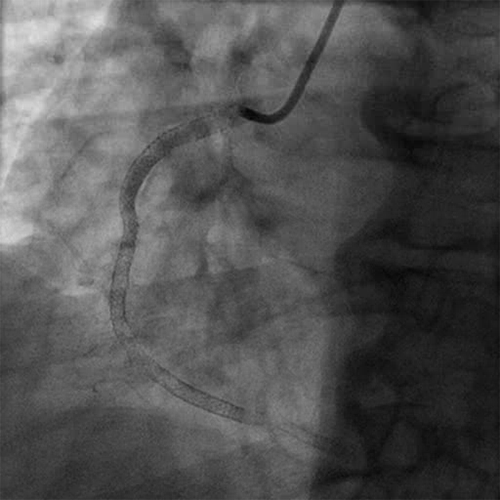

• The RCA was treated with ANGIOJET thrombectomy utilizing the SPIROFLEX catheter

• There was residual thrombus in the mid and distal stents (Cine 2: AngioJet)

• Initially the mid and distal RCA into the posterior lateral artery were treated with multiple SPIROFLEX passes for a total of 27.5 seconds

• A second series of runs was performed utilizing SPIROFLEX ANGIOJET for a total of 35 seconds